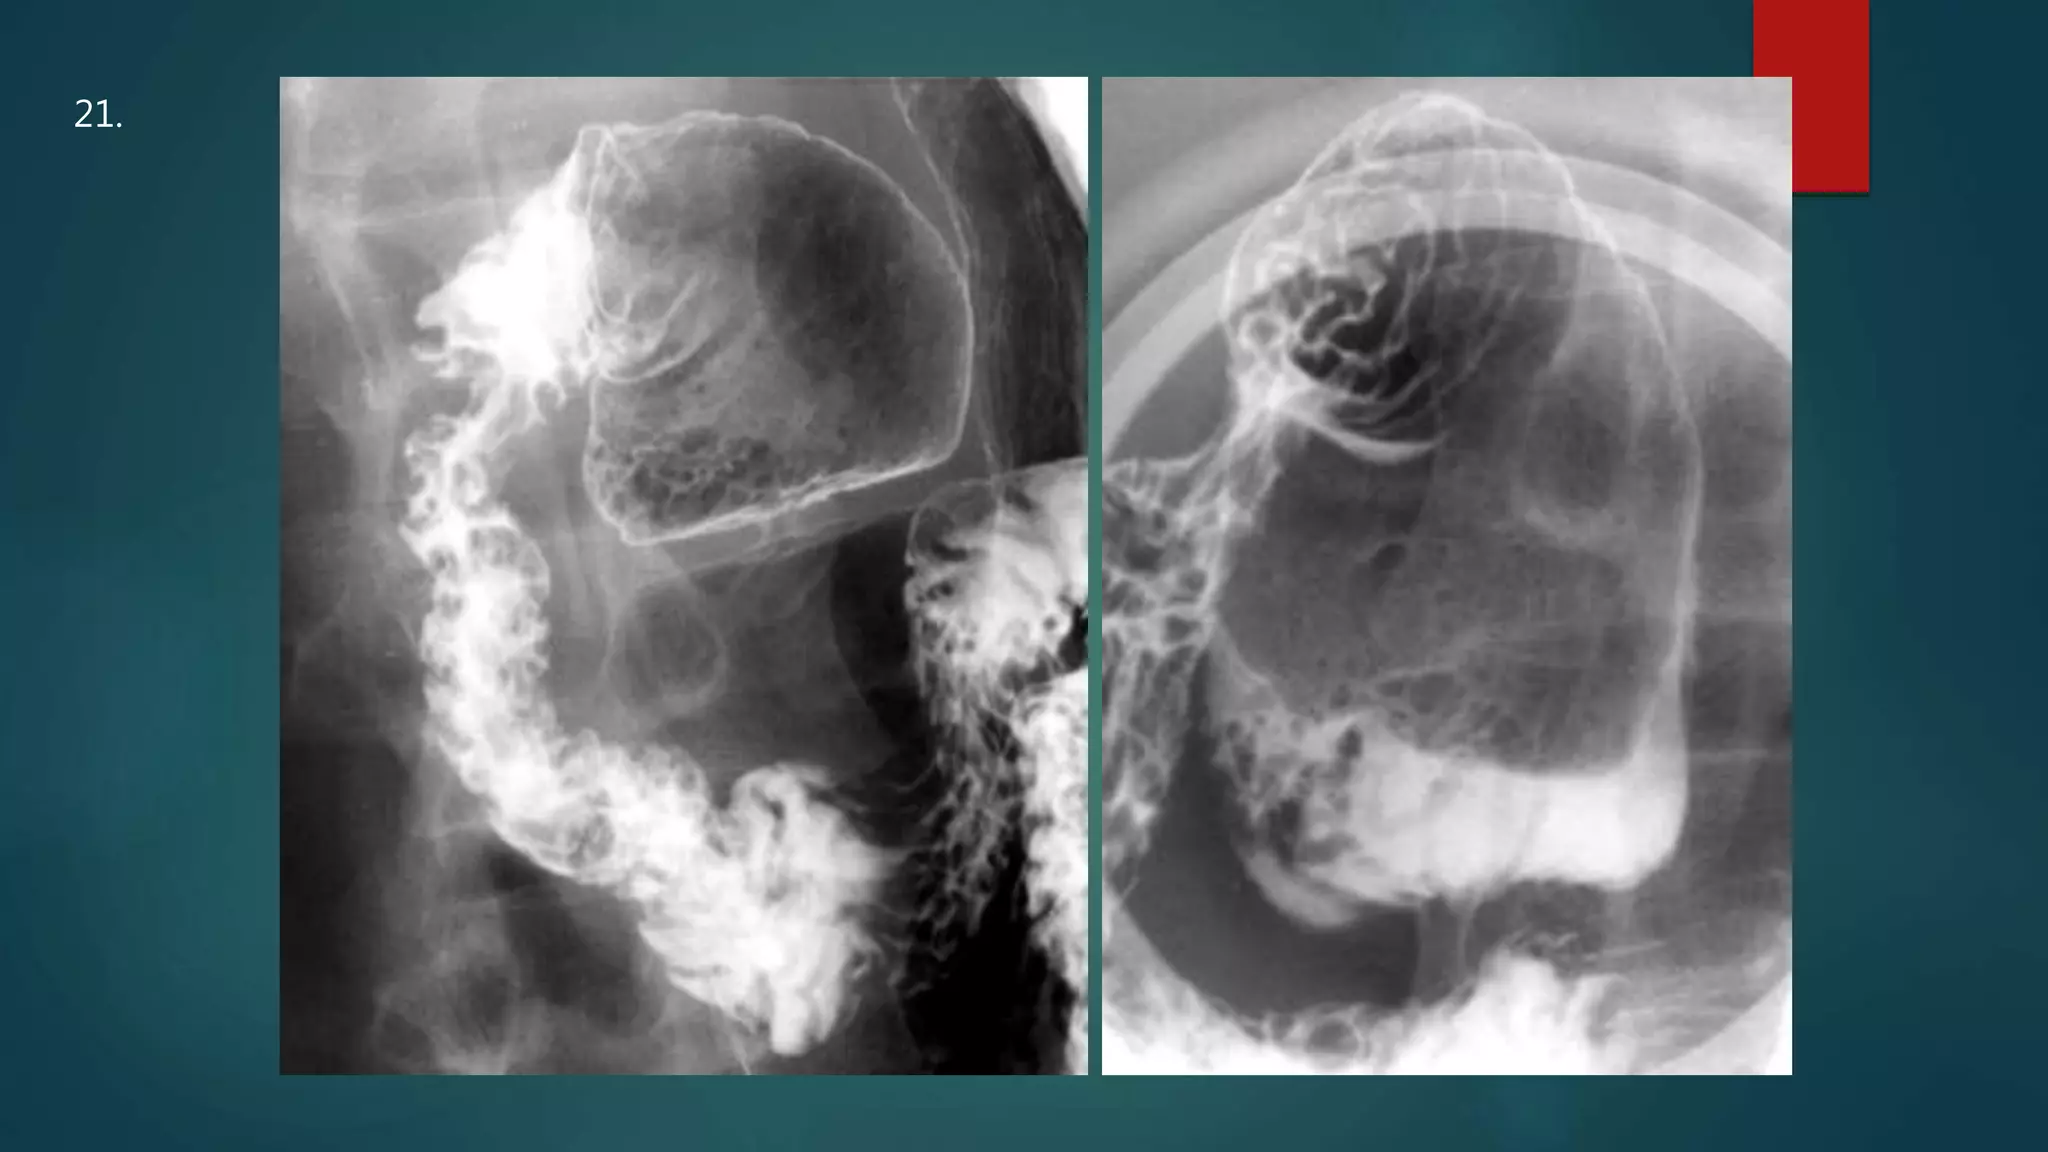

This document appears to be a medical report discussing several patients. It mentions a 35-year-old who was in a severe motor vehicle accident and an 81-year-old with a history of a non-vegetarian diet who had a perforated bowel from a chicken bone. The document provides few other details across its 25 numbered entries and was authored by Dr. Anish Choudhary for junior year 3 on May 30, 2016.